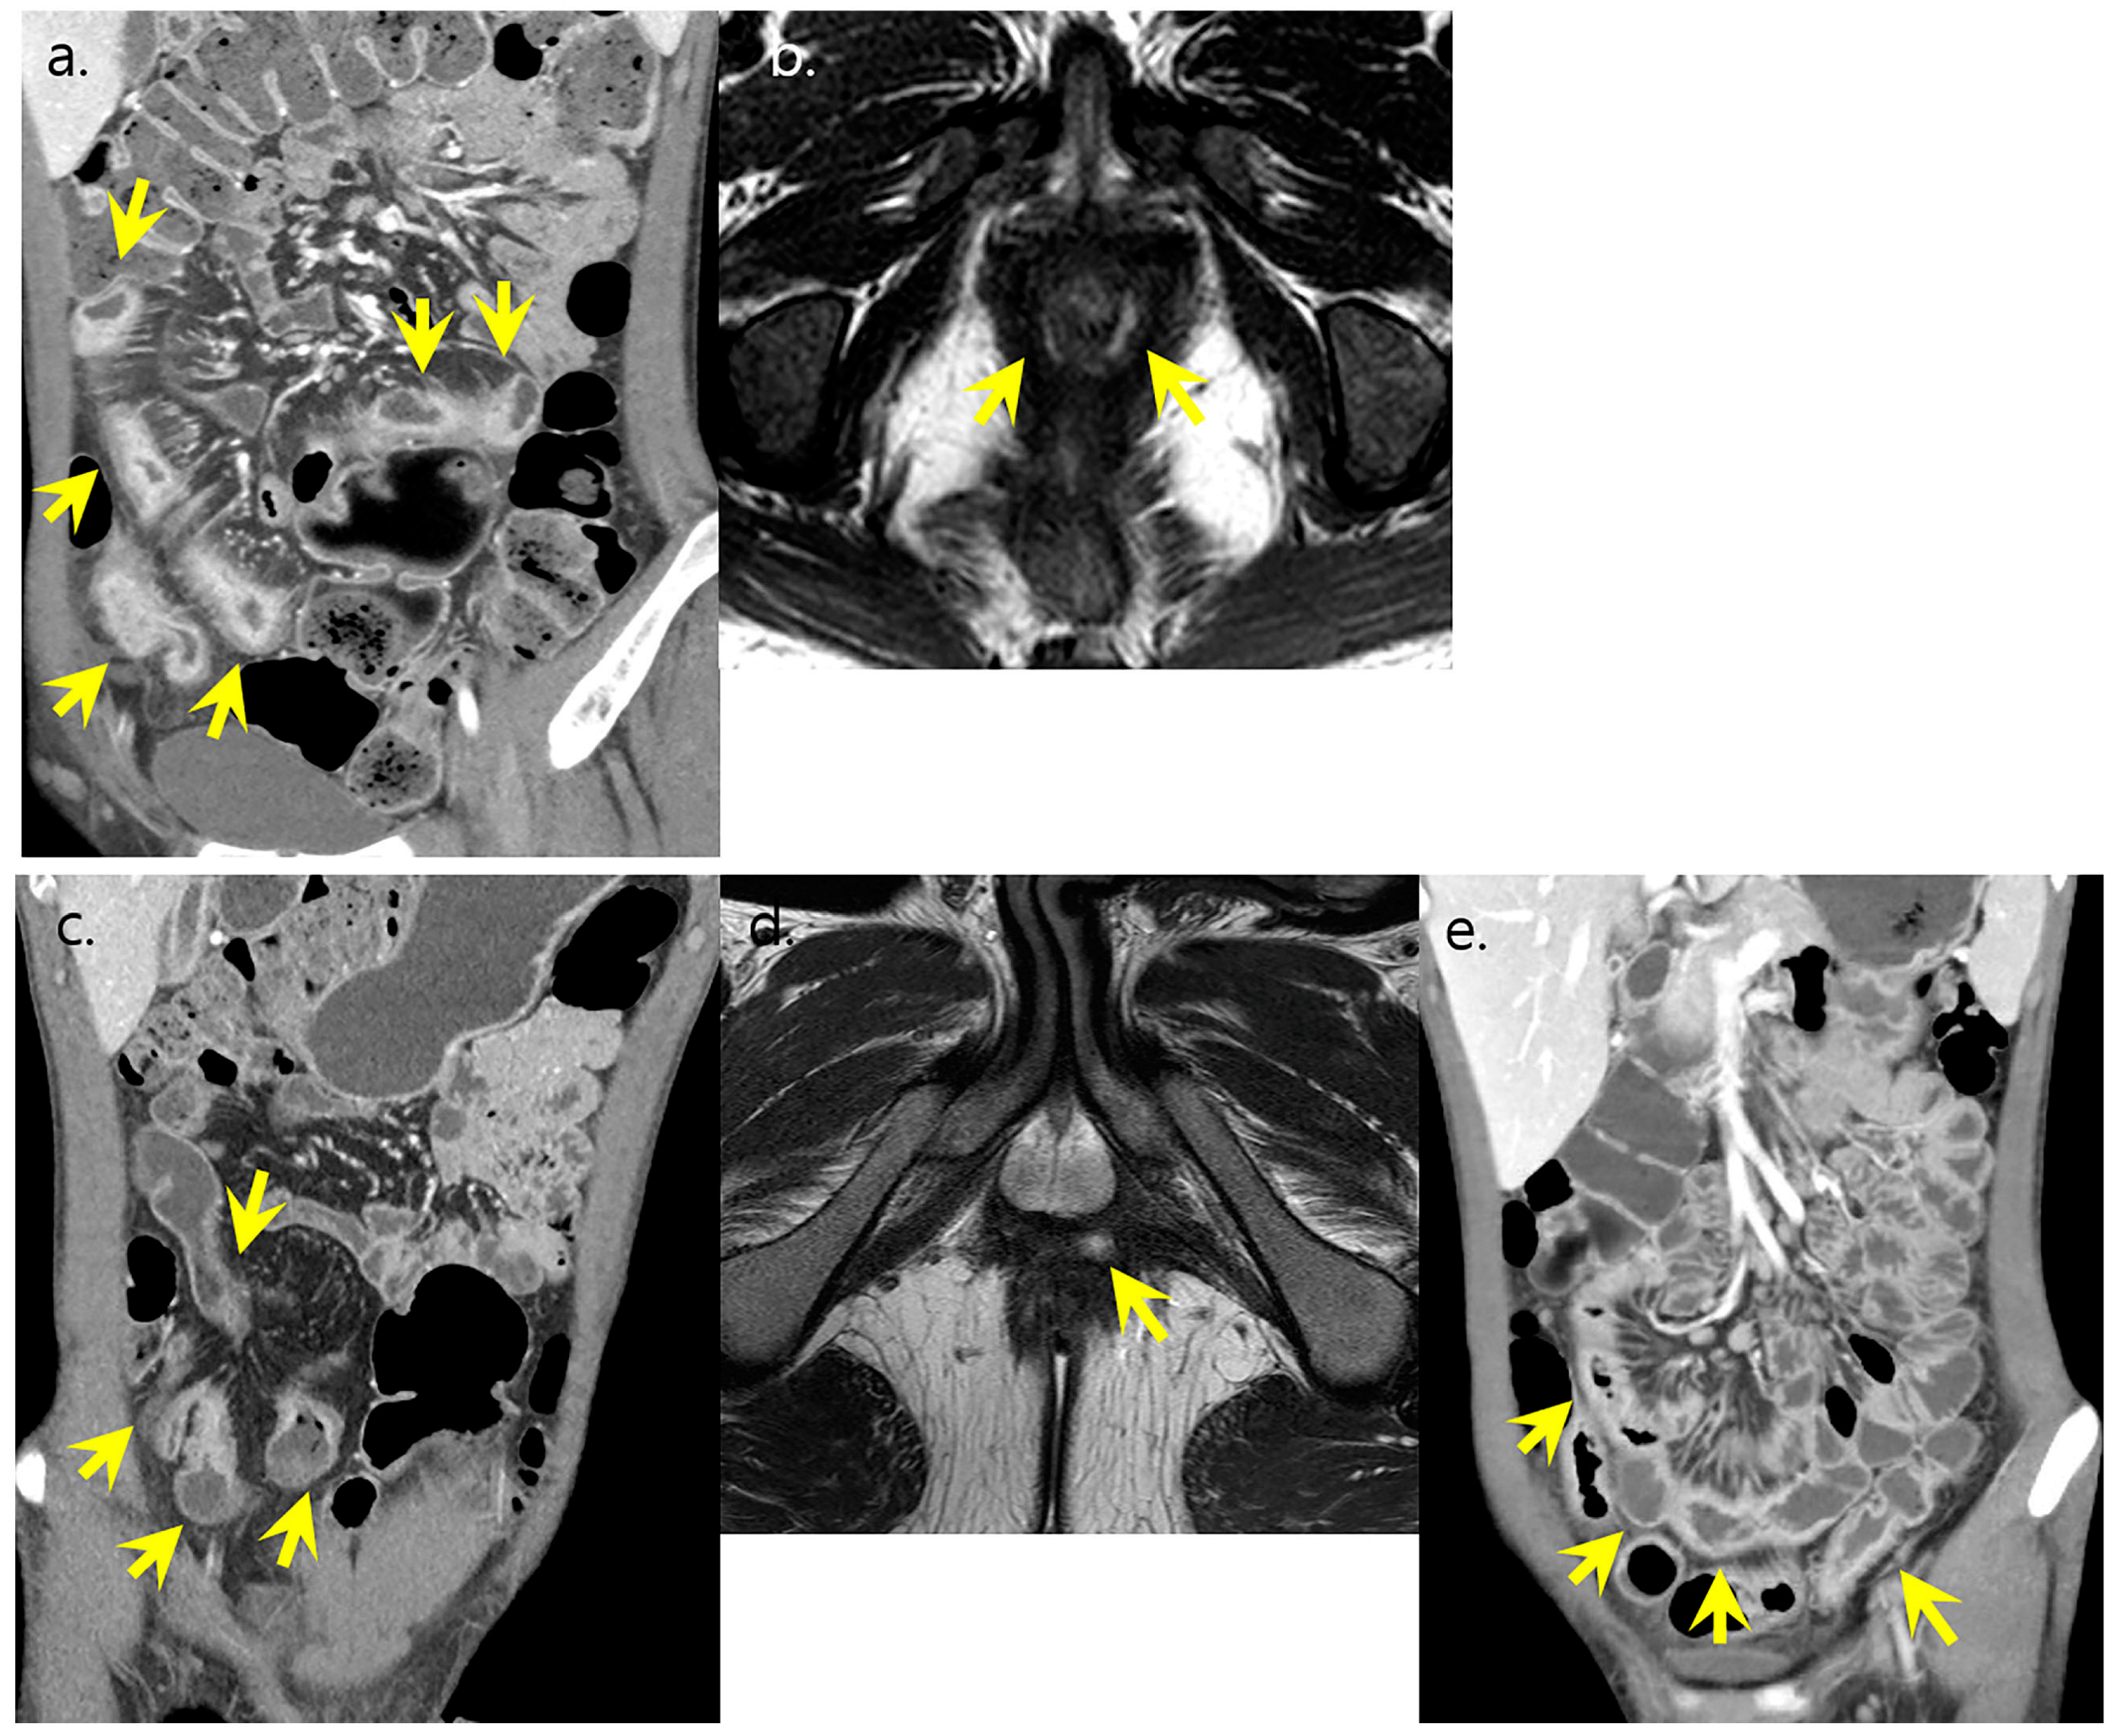

2.3. Radiologic and Endoscopic Analyses of Disease Pattern